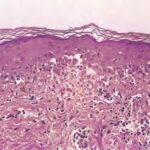

Histopathology. EM is considered the prototype of the vacuolar form of interface dermatitis . The early changes include vacuolization of the basal cell layer; tagging of lymphocytes along the dermal-epidermal junction; and a sparse, superficial, perivascular lymphoid infiltrate . Necrosis of individual keratinocytes in the basal unit occurs, which is the hallmark of EM. Because of its acute nature, there is an orthokeratotic stratum corneum. Mild spongiosis, papillary dermal edema, and extravasation of red blood cells are seen. As the lesion becomes more developed, there is a moderate lichenoid infiltrate of Iymphohistiocytes at the dermal-epidermal junction with exocytosis. More apoptotic keratinocytes within and above the basal epidermal layer are present. The |

intensity of epidermal necrosis varies from vacuolated individual keratinocytes surrounded by lymphocytes (satellite cell necrosis) at the basal unit to confluent necrosis in association with intraepidermal and subepidermal vesicles. The dermal infiltrate comprises lymphocytes and histiocytes. Eosinophils may also be present. Although one study has noted a significant number of eosinophils in drug-induced EM, this has not been noted by others. In the authors’ estimation, a generous number of eosinophils exclude EM. One study has found that an acrosyringium concentration of apoptotic keratinocytes in EM is a clue to a drug etiology . In early lesions of SJSITEN, apoptotic keratinocytes are observed scattered in the basal layer of the epidermis. In established lesions, there are numerous necrotic keratinocytes, even full-thickness epidermal necrosis, and a subepidermal bulla. The dermal inflammatory infiltrate is sparser in TEN than in EM (Fig. 9-278). Extravasated erythrocytes are commonly found within the blister cavity. Melanophages within the papillary dermis occur in late lesions. Eccrine epithelium shows a variety of changes from basal cell apoptosis to necrosis of the duct. |

In general, EM shows less epidermal necrosis, more dermal inflammation, and exocytosis, whereas SJS and TEN reveal more epidermal necrosis, less dermal inflammation, and exocytosis. However, due to the overlapping histologic features among EM, SJS, and TEN, histologic examination-while important for recognizing the spectrum of disorders-is not reliable for classifying the disease. Correlation with clinical presentation is essential. |